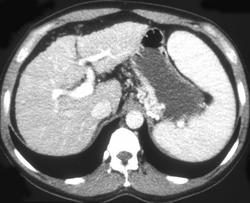

Gastric Cancer With Nodes and Adrenal Mets